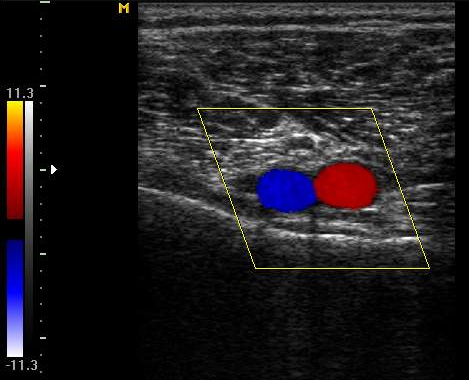

Цветная картинка является более наглядной и удобной в использовании: направление тока крови определяется и выделяется синим или красным цветом, а оттенок свидетельствует о скорости течения в данном сосуде.

Триплексное сканирование это распространенное называние сочетания дуплексной допплерометрии с цветовым картированием.

Проксимальную компрессию считают причиной расширения берцовых вен в 1,5-2 раза. В таких случаях клапаны приобретают четкий характер. Если просвет сосуда показывается при цветовом кодировании как эхонегативный, значит, в нем отсутствует ретроградный кровоток.

Если просвет окрашен в синий цвет, а допплеровский шум усилился, это является признаком выраженного антеградного кровотока (результата декомпрессии).

Дистальная компрессия характеризуется синим цветом кровотока на мониторе и усилением сигнала допплерографа. Если устранить компрессию, то просвет сосуда станет эхонегативным, а сигнал почти исчезнет.